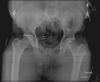

23

MALGAIGNE

- Fracture of the ilium near the sacroiliac joint with displacement of the symphysis, or a dislocation of the sacroiliac joint with fracture of both ipsilateral pubic rami

- unstable pelvis